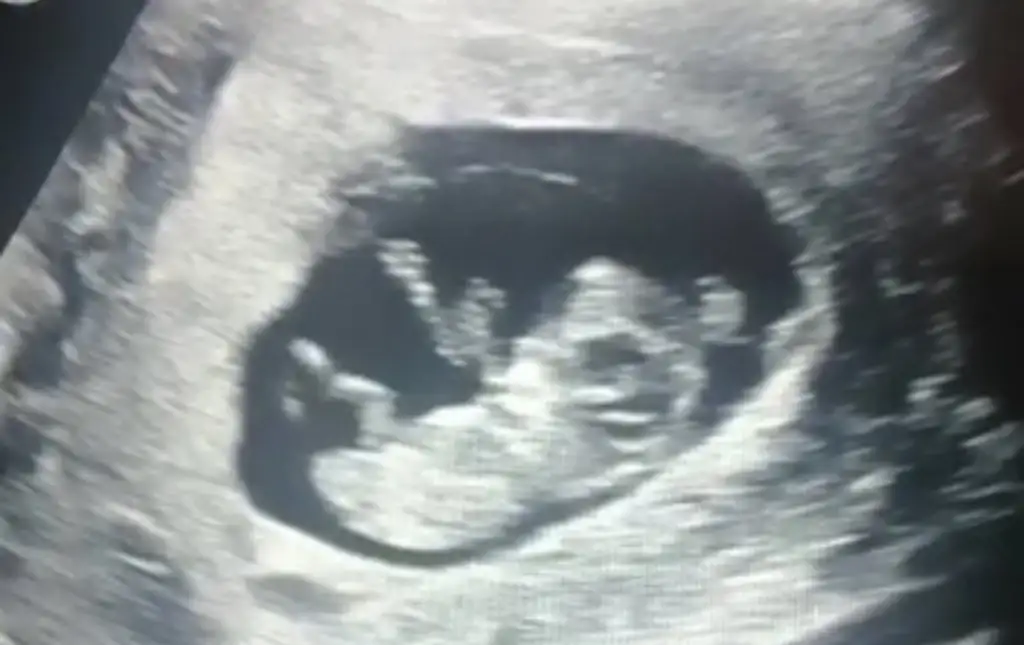

Bebeğimin cinsiyeti

12+6 dedi

Kızlarrrrrrrrr çok şükür ikili testim temiz çıktı. 10 binde 1 dedi çok çok düşük dedi çok şükür. Cinsiyeti yüzde 80 oranıyla söyledi kağıda yazdırdım akşam size söylicem 😂❤️